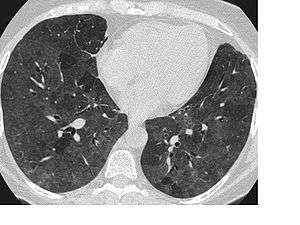

High-resolution CT: increase in density in areas of ground glass and air trapping in lower lobes in patients with hypersensitivity pneumonitis.

In radiology, ground glass opacity (GGO) is a nonspecific finding on computed tomography (CT) scans that indicates a partial filling of air spaces in the lungs by exudate or transudate, as well as interstitial thickening or partial collapse of lung alveoli. The similarity of shadows to a real ground glass is obvious.